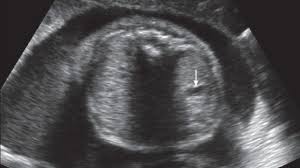

Hamil 11 Minggu Janin Sebesar Apa / Apa yang terjadi pada usia hamil 11 minggu?. Apakah usia janin 8 minggu itu sudah berbentuk, janin 11 minggu sebesar apa, janin 9 minggu 2.2 cm, panjang janin 10 minggu, panjang janin 7 minggu, saiz janin 2 bulan, saiz janin 9 minggu, ukuran janin 10 minggu, ukuran janin 2 bulan sebesar. Janin anda 11 minggu sekitar 1,6 inci dan beratnya sekitar 0,25 ons. Memasuki usia kehamilan 11 minggu, anda tetap perlu melakukan pemeriksaan medis guna memastikan jika kehamilan berjalan dengan baik. Hallo bunda semua,, apa kabar? Pada periode ini, janin dalam kandungan terus mengalami perkembangan.

Janin tersebut dengan rasio 1: Saat hamil 11 minggu banyak wanita yang mengalami keputihan. Jika saat pemeriksaan dokter m. Mata, telinga, dan mulut masih terus tumbuh dan berkembang dan wajah calon bayi kini makin terlihat jelas. Janin anda 11 minggu sekitar 1,6 inci dan beratnya sekitar 0,25 ons. Pada kehamilan 11 minggu, sejumlah perkembangan yang terjadi pada janin anda adalah sebagai berikut: Tapi masih ragu nih bunda mau cek kebidan, masalahnya. Apakah ibu hamil 11 minggu sudah mulai membesar?

See full list on doktersehat.com Apakah ibu hamil 11 minggu sudah mulai membesar? Namun, ibu pun akan mengalami keluhan berupa asam lambung yang naik, wasir, hingga jantung berdebar. 1 ukuran kepala berbanding tubuh. See full list on doktersehat.com Apa yang terjadi pada usia hamil 11 minggu? Feb 17, 2012 · ts. Ukuran janin 11 minggu sudah sebesar buah ara dengan panjang dari atas sampai ke bawah kurang lebih 4 cm dan berat 7 gram.